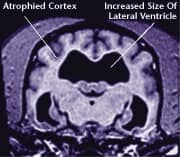

![]() Healthy Older Brain | ![]() Older Brain with Damage |

MRI scans show loss of brain tissue in affected dogs. Note: MRI scans are not harmful to dogs. |